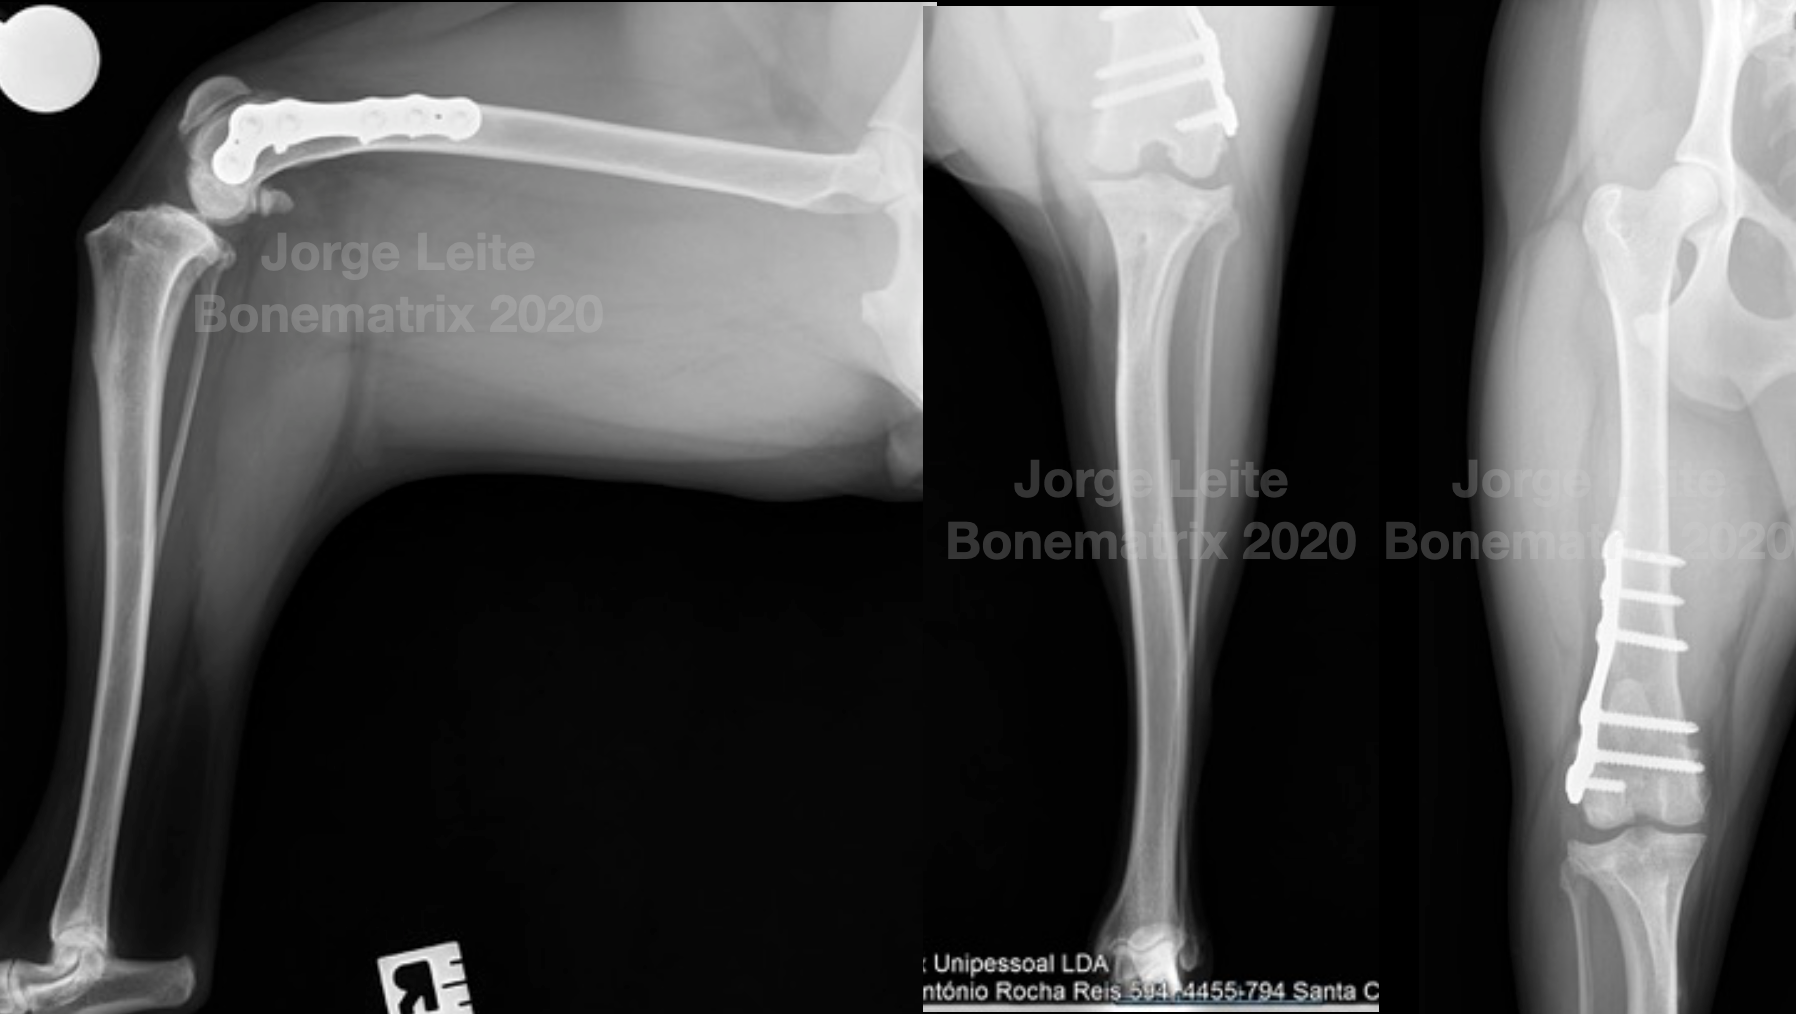

Mesmo cão, necessidades diferentes para tratamento de luxação medial de patela nos dois joelhos.

Esta semana fizemos o segundo joelho.

Luxação medial de patela grau II com severo desconforto de joelho devido a erosão de cartilagem e osteoartrite.

Este paciente foi tratado à 2 anos ao membro contra-lateral com DFO + TTT (já removeu o espaçador)